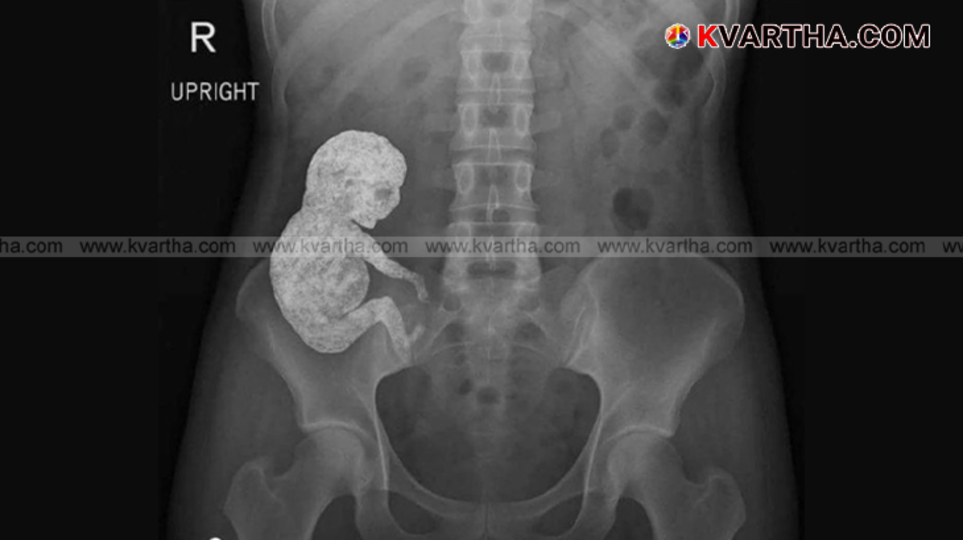

(KVARTHA) സമൂഹമാധ്യമങ്ങളിൽ ഒരു ഡോക്ടർ പങ്കുവെച്ച എക്സ്-റേ ചിത്രം കണ്ട് ലോകം അമ്പരപ്പിലാണ്. 'ലിത്തോപീഡിയൻ' അഥവാ 'സ്റ്റോൺ ബേബി' എന്നറിയപ്പെടുന്ന, അതീവ അപൂർവമായ ഒരു മെഡിക്കൽ അവസ്ഥ വെളിപ്പെടുത്തുന്നതായിരുന്നു ആ വിചിത്രമായ ചിത്രം.

ഡോ. സാം ഖാലി തന്റെ എക്സ് (മുമ്പ് ട്വിറ്റർ) ഹാൻഡിലിലൂടെ പങ്കുവെച്ച ഈ ചിത്രം നിമിഷനേരം കൊണ്ട് ലക്ഷക്കണക്കിന് ആളുകളിലേക്കാണ് എത്തിയത്. ഒരു സ്ത്രീയുടെ ശരീരത്തിനുള്ളിൽ എല്ലുകൾ കൊണ്ട് രൂപപ്പെട്ട ഒരു കുഞ്ഞിനെ കണ്ടവർക്കെല്ലാം അത്ഭുതവും ഞെട്ടലുമായിരുന്നു ഫലം.

‘ഞാൻ ഇതുവരെ കണ്ടിട്ടുള്ളതിൽ വെച്ച് ഏറ്റവും ഭ്രാന്തമായ എക്സ്-റേകളിൽ ഒന്ന് ഇതാ,’ എന്ന കുറിപ്പോടെയാണ് ഡോ. സാം ഖാലി ഈ ചിത്രം പങ്കുവെച്ചത്. ’എന്താണ് രോഗനിർണയം?’ എന്നും അദ്ദേഹം ചോദിച്ചു.

ആ എക്സ്-റേ ചിത്രത്തിൽ, ഒരു സ്ത്രീയുടെ ഇടുപ്പിന് സമീപത്തായി കാൽസ്യം നിറഞ്ഞ ഒരു ഗർഭസ്ഥ ശിശുവിന്റെ രൂപം വ്യക്തമായി കാണാമായിരുന്നു. അസാധാരണമായ ഈ ചിത്രം കണ്ട പലരും ഇത് നിർമിത ബുദ്ധിയുടെ (AI) സഹായത്തോടെ നിർമിച്ചതാണോ എന്ന് സംശയം പ്രകടിപ്പിച്ചു. എന്നാൽ, ചിത്രത്തിന് താഴെ നൽകിയ കുറിപ്പിലൂടെ ഡോ. സാം ഖാലി ഈ ഗർഭസ്ഥ ശിശുവിന്റെ നിഗൂഢത വെളിപ്പെടുത്തി.

‘ഉത്തരം: ലിത്തോപീഡിയൻ,’ അദ്ദേഹം കുറിച്ചു. തുടർന്ന്, ലിത്തോപീഡിയൻ അവസ്ഥ എന്താണെന്ന് മറ്റൊരു കുറിപ്പിൽ വിശദീകരിച്ചു. എക്ടോപിക് ഗർഭാവസ്ഥയുടെ (ഗർഭപാത്രത്തിന് പുറത്ത് ഭ്രൂണം വളരുന്ന അവസ്ഥ) വളരെ അപൂർവമായ ഒരു സങ്കീർണതയാണ് ലിത്തോപീഡിയൻ. ഗ്രീക്ക് പദങ്ങളായ 'ലിത്തോസ്' (കല്ല്), 'പീഡിയൻ' (കുട്ടി) എന്നിവയിൽ നിന്നാണ് ഈ പദം ഉരുത്തിരിഞ്ഞതെന്നും, അതുകൊണ്ടാണ് ഇത്തരം കുട്ടികളെ 'കല്ല് കുട്ടി' അല്ലെങ്കിൽ 'കല്ല് കുഞ്ഞ്' എന്ന് വിളിക്കുന്നതെന്നും അദ്ദേഹം കൂട്ടിച്ചേർത്തു.

ഗർഭപാത്രത്തിന് പുറത്ത് വളരുന്ന ഒരു ഭ്രൂണം ആദ്യ മൂന്ന് മാസത്തിനപ്പുറം വളരുകയും പിന്നീട് മരണപ്പെടുകയും ചെയ്യുമ്പോഴാണ് ഈ അവസ്ഥ ഉണ്ടാകുന്നത്. അമ്മയുടെ രോഗപ്രതിരോധ സംവിധാനം ഈ മരിച്ച ഭ്രൂണത്തെ ശരീരത്തിന് പുറത്തുനിന്നുള്ള ഒരു വസ്തുവായി കണക്കാക്കുന്നു.

തുടർന്നുണ്ടാകാൻ സാധ്യതയുള്ള അണുബാധ തടയുന്നതിനായി, ശരീരം ഈ ഭ്രൂണത്തെ കാൽസ്യം ഉപയോഗിച്ച് പൊതിഞ്ഞ് സംരക്ഷിക്കുന്നു. ഇത്തരത്തിൽ കൂടുതൽ കാൽസ്യം അടിഞ്ഞുകൂടുന്നതിനാലാണ് ഇവയെ 'സ്റ്റോൺ ബേബി' എന്ന് വിളിക്കുന്നതെന്ന് ഡോക്ടർ വിശദീകരിക്കുന്നു.

ഇത്തരം സംഭവങ്ങൾ സാധാരണയായി രോഗലക്ഷണങ്ങളില്ലാതെ വർഷങ്ങളോളം ശ്രദ്ധിക്കപ്പെടാതെ കിടക്കാറുണ്ട്. ശസ്ത്രക്രിയയ്ക്കിടെയോ മറ്റ് വൈദ്യപരിശോധനകളുടെ ഭാഗമായി മെഡിക്കൽ ഇമേജിംഗ് നടത്തുമ്പോഴോ മാത്രമാണ് ഇവ കണ്ടെത്തപ്പെടുന്നത്.